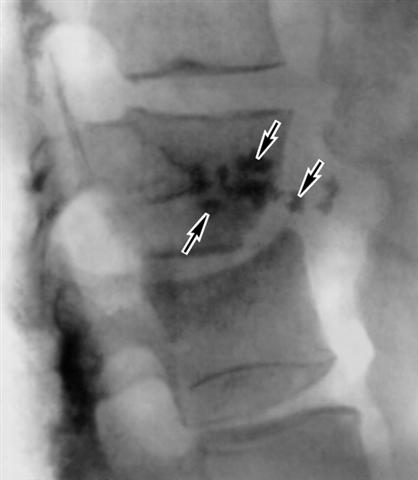

Рис. 4. Рентгенограмма поясничного отдела позвоночника при туберкулезном спондилите (боковая проекция): контактная деструкция в телах двух позвонков, разрушение межпозвоночного диска, нечеткие контуры пораженных позвонков, секвестры (указаны стрелками). |